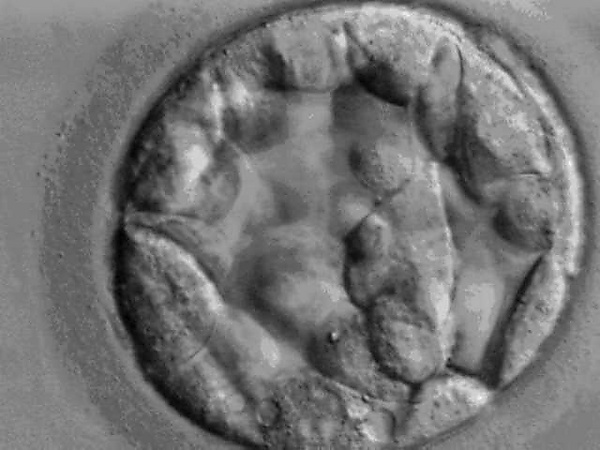

Выход эмбриона из zona pellucida

После достижения стадии бластоцисты эмбриону требуется выйти из блестящей оболочки, чтобы приступить к имплантации. Процесс выхода из zona pellucida называется хетчинг (англ. hatching — вылупление). Эмбрион человека совершает хетчинг на 5-7 день развития, эмбрион мыши на 4-5 день развития. Механизм выхода сложен. Разрыв оболочки обусловлен двумя факторами: механическим воздействием эмбриона (бластоциста наполняет свою полость водой и увеличивается в размере, давя на стенки zona pellucida изнутри), химическим воздействием эмбриона (трофэктодерма эмбриона выделяет протеолитический фермент «стрипсин», который растворяет оболочку). Эмбрион (бластоциста) покидает zona pellucida, выходя через образовавшуюся щель с помощью «амебоидных» движений.